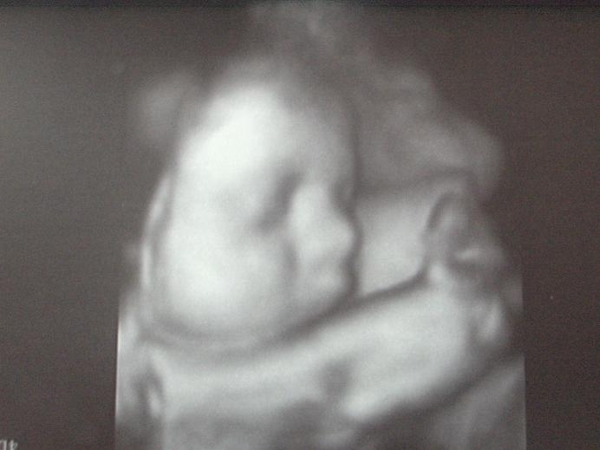

Mi tylko dwa razy,pierwsze w 15 a drugie w 23 tygodniu.

teraz zapytałam o trzecie i wypisał mi skierowanie, bo przecież można zrobic badanie, ale wypisał tylko dlatego że zapytałam, bo wcześniej powiedział że już nie będzie potrzebne.

A mnie tu jeszcze zastanawia takie coś "położenie podłużne miednicowe,

ustawienie II ". Czy to jest dobre ułożenie dziecka? Bo ja gdzieś w necie kiedyś wyczytałam że takie położenie oznacza że dziecko ma główkę do góry, a powinno mieć do dołu... Z tym ułożeniem to jest tak że ona się zmienia pod koniec ciąży ale jesli mam rację i ułożenie mojego dziecka było w 23 tyg. odwrotne to chyba powinni sprawdzić czy się przekręciło( przekręci)... ?